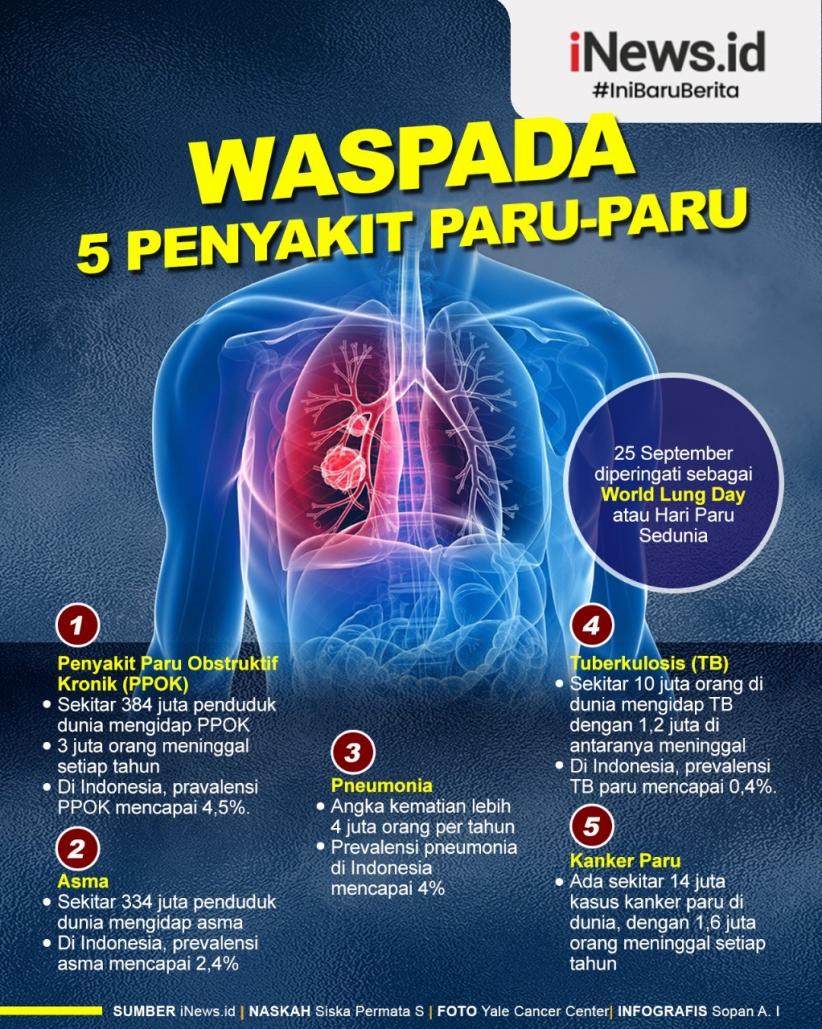

Infografis 5 Penyakit Berbahaya Menyerang Paru Paru